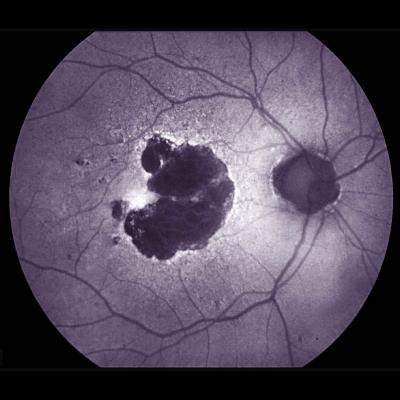

Photo of retina with large dark splotch to left of optic nerve.

Retinal photo showing large area of geographic atrophy. Image credit: NEI.

Dry AMD affects the macula, the part of the eye’s retina that allows for clear central vision. In people with dry AMD, patches of light-sensing photoreceptors and their nearby support cells begin to die off, leaving regions known as geographic atrophy. Over time, these regions expand, causing people to lose more and more of their central vision. Microglia, immune cells that help maintain tissue and clear up debris, are present at higher levels around damaged retinal regions in people with dry AMD than in people without AMD. Scientists have suggested that inflammation – and particularly microglia – may be driving the expansion of geographic atrophy regions.